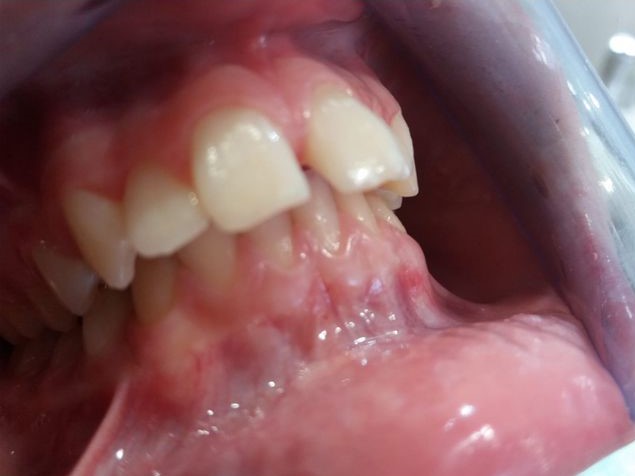

Vamos a ver el tratamiento de ortodoncia de un paciente de 11 años de edad en el que se observa una clase II de tipo dento-alveolar. Tiene un perfil de ligera protrusión del maxilar superior y retrusión de la mandíbula. Los incisivos inferiores llegan a contactar con el paladar superior pero muy hacia atrás. Esto le da un perfil de pájaro. Siendo la causa diversa en las que se mezcla diferentes parafunciones como interposición del labio inferior entre los dientes incisivos superiores e inferiores, o también interposición lingual al tragar etc. Es decir son los músculos (labio, lengua etc.) con sus malos hábitos los que producen las mal oclusiones e incluso trastornos del desarrollo óseo maxilomandibular normal. Es decir los músculos de la cara son los arquitectos de los huesos faciales, en este caso que exponemos para mal.